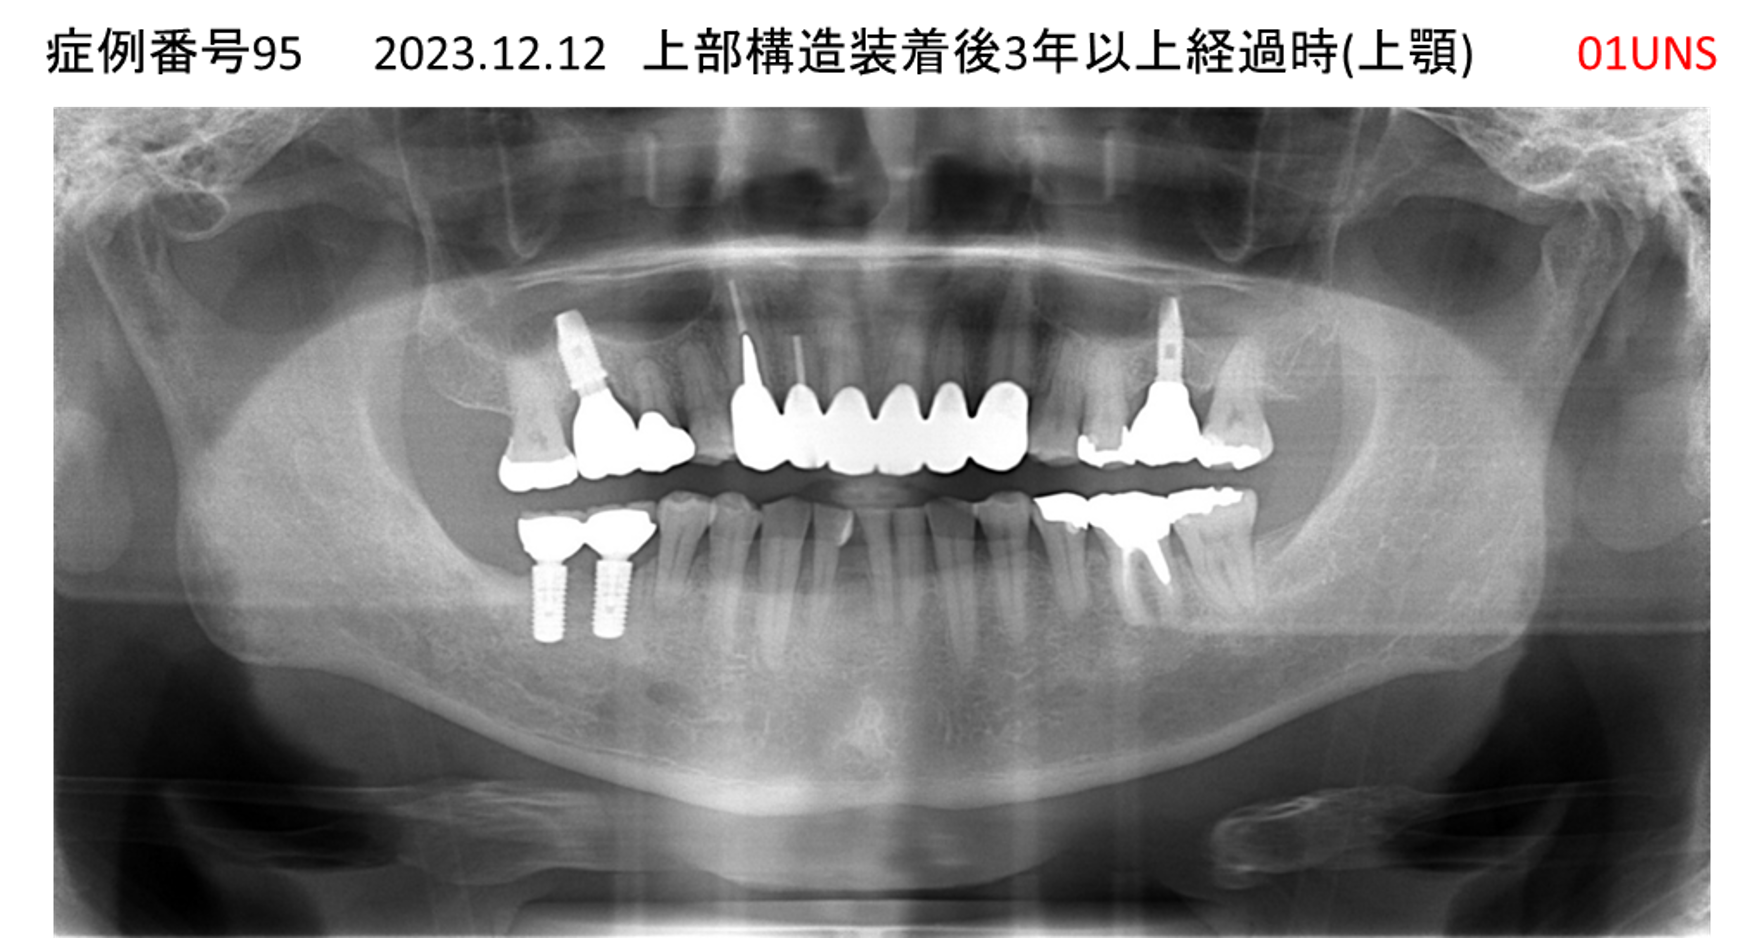

上の前歯が揺れてきてかめない患者様のインプラント症例

| 治療名称 |

インプラント |

| 治療費用 |

440万円+税 |

| 治療期間 |

6か月 |

| 患者さんの症状(主訴) |

上の前歯が揺れてきた。かめない |

| 治療内容 |

サイナスリフト、GBR、インプラント、即時荷重 |

| 治療結果 |

上の前歯の揺れが収まった。奥歯でしっかり噛める。 |

| 治療の注意点(リスク/副作用) |

インプラントが壊れたら再治療が必要 |